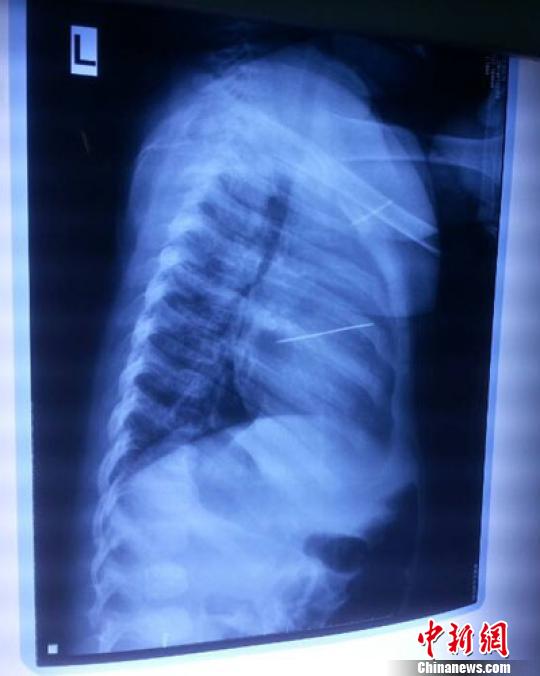

女嬰胸片提示心臟里面扎了一個(gè)縫衣針 蔡迅翔 攝

醫(yī)院胸心外科主任翟波介紹說,1月22日,小患者彤彤因?yàn)榘l(fā)燒抽搐來醫(yī)院就診,常規(guī)檢查時(shí)發(fā)現(xiàn)孩子心臟里面扎了一個(gè)縫衣針。

“第二天上午,我們做了個(gè)緊急彩超檢查,發(fā)現(xiàn)針是從患者右心室表面刺入,穿破室間隔,到達(dá)左心房,中間還有一部分損害到二尖瓣。于23號(hào)下午,我們就做了一個(gè)緊急手術(shù),手術(shù)中發(fā)現(xiàn),這枚針已經(jīng)刺入心臟,沒入了右心室的下面,表面已經(jīng)看不到針了,僅能看到一個(gè)小針眼,還在往外滲血,一點(diǎn)一點(diǎn)的滲,心包腔里面大概有100多毫升的出血,心包上一個(gè)洞,針在右心室表面刺入以后,穿過室間隔,在二尖瓣的上方,進(jìn)入了左心房,在針的四周,有很多纖維沉積物,包繞著這枚針。”翟波說,他們把針取出來以后,測(cè)量了一下,長度大概是五厘米,同時(shí)發(fā)現(xiàn)這個(gè)針給患者左心房的后壁造成了一定的損傷,左心房的后壁已經(jīng)損傷了三分之二,還剩下有左心房的外膜,很薄的一層,如果這一層再破的話,這個(gè)孩子將會(huì)引起大出血,很快就會(huì)死亡。